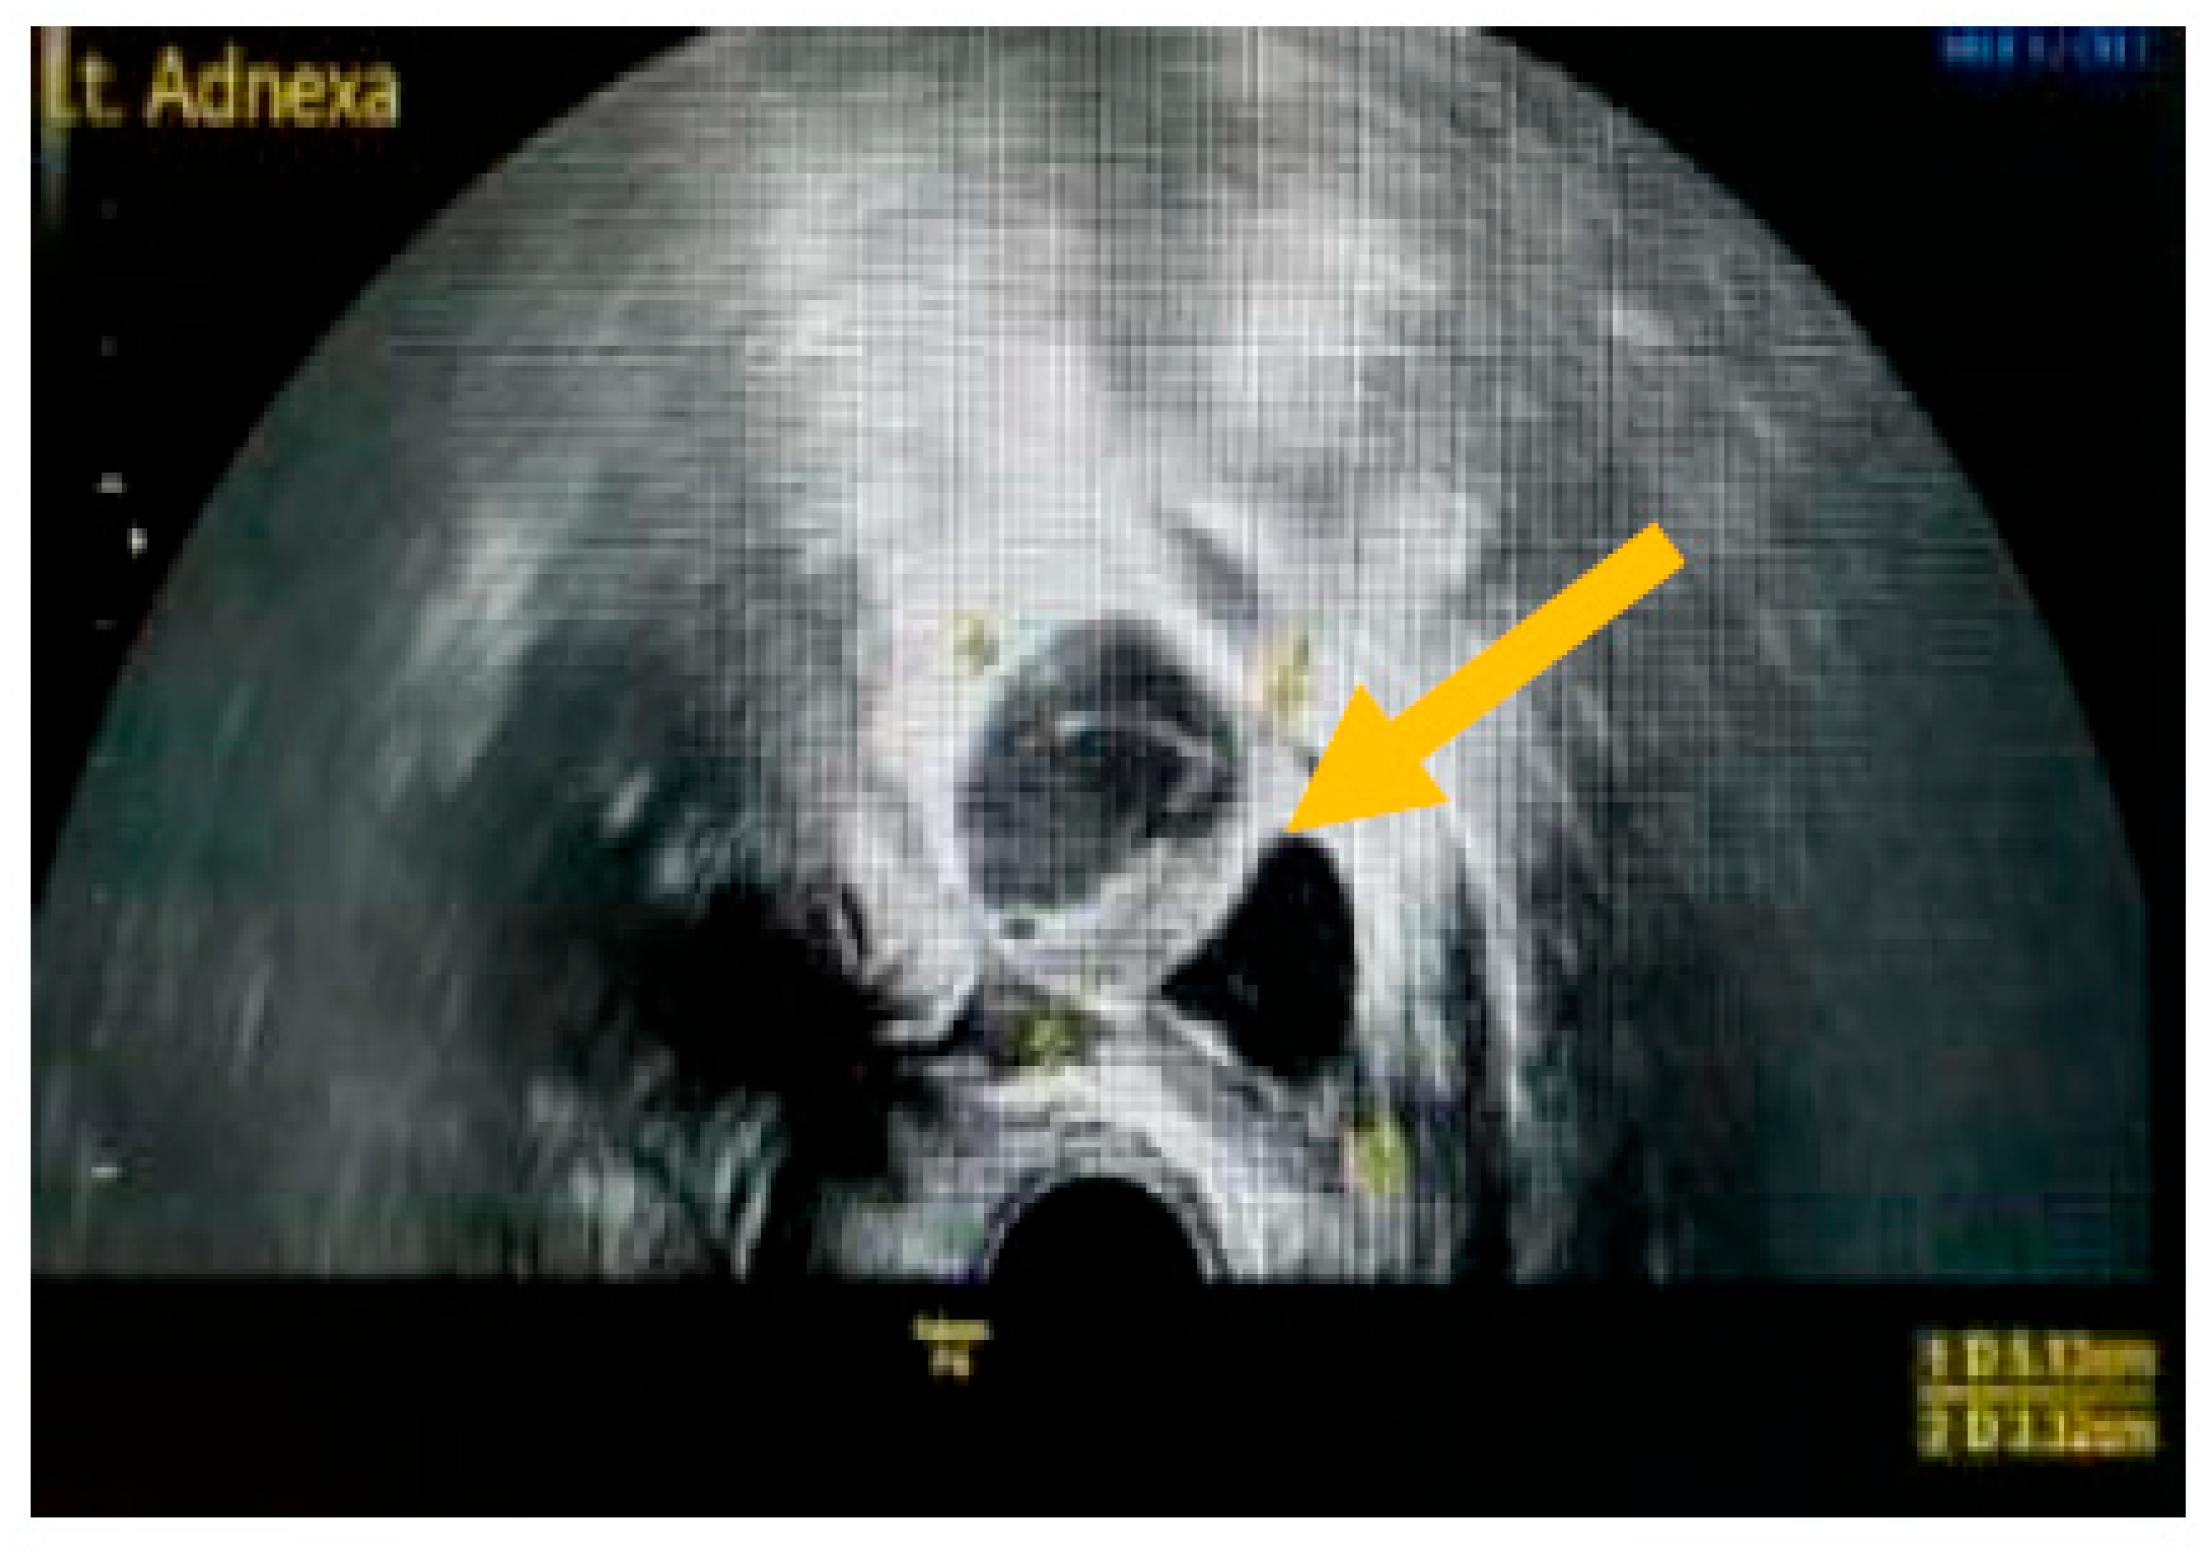

The existence of irregular solid tumors, ascites, at least four papillary structures, an irregular multilocular-solid tumor (diameter at least 10 cm), and very strong blood flow on a color Doppler assessment are malignant indicators, whereas a unilocular cyst, the presence of solid components (max diameter < 7 mm), the presence of an acoustic shadow, a smooth multilocular tumor (max diameter < 10 cm), and the absence of detectable blood flow on the Doppler predispose for the presence of a benign mass [24] (Figure 1, Figure 2 and Figure 3).

Figure 3.

Presence of solid component. (Yellow arrow indicates a multilocular solid cyst with a measurable solid component).